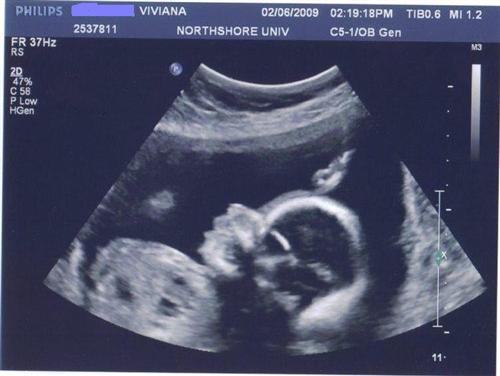

22 weeks 5 days